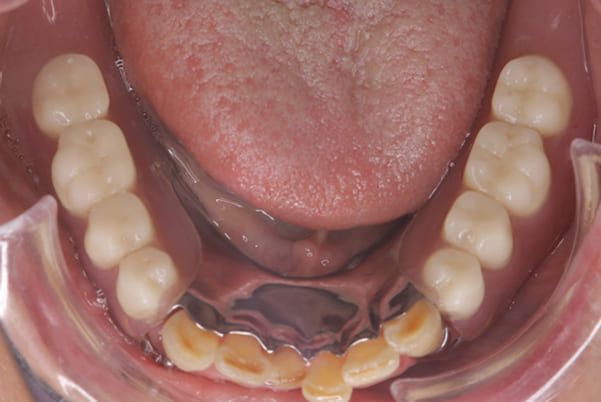

下顎治療後

治療前の入れ歯の奥歯は、治療後の義歯と比較しても分かるように、歯が削れ平らになった状態です。

これにより奥歯のかみ合わせは低くなり、前歯のみが強くあたり、かみ合わせにより上の前歯大きな負担がかかっていたことにより、上の前歯が折れたことが考えられます。

治療用入れ歯は患者様とご相談し、早急にお痛みをとり、お食事ができることをご希望されていたため、歯を抜くと同時に仮の入れ歯が入りお食事をされた後のお写真です。直ちに、お痛みを取り除き、お食事ができるような治療計画としました。

精密義歯は、歯をぬいたあと歯肉が治ってから、精密な入れ歯を作製しました。治療中も、仮の入れ歯があるため、普段の生活に支障がなく、また仮の入れ歯を実際使ってのご意見、ご希望(バネが気になる)をお聞きした上で、精密な義歯に、ご希望を反映し作製しました。

従来の方法では、歯を抜いてから入れ歯を作るまでは、歯茎の治りを待つため数か月かかりますが、患者様のご希望で、見た目、食べることに支障が出ないよう、抜歯と同時に入れ歯を装着し、歯がない期間がない入れ歯を作製したため、その日から、お食事や外出が可能となりました。

また、当然ではありますが、患者様も残りの歯をこれ以上失いたくないとのご希望が強く可能な限り、残りの歯に負担がかからない機能性を重視し、また、バネがなるべく見えない設計とし、機能と審美の両方に重きをおいた入れ歯を作製し、お痛みなく、お食事も召し上がられるようになりました。